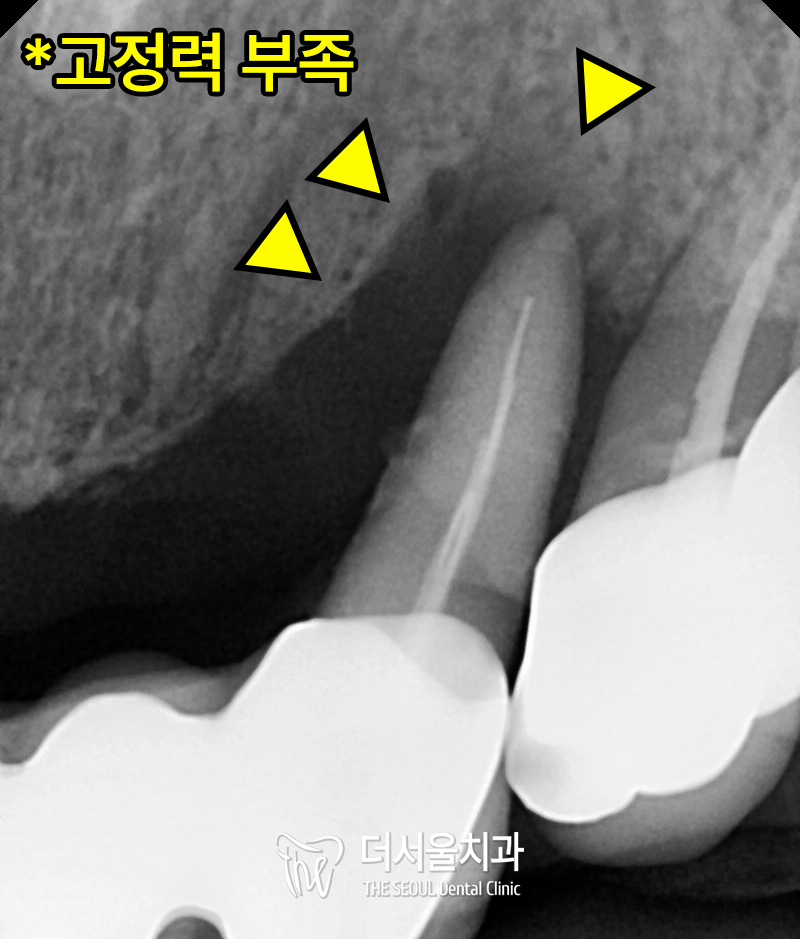

앞서 설명드렸던

치조골 퇴축이 전체적으로 관찰되었으며

맞닿는 대합치가 없는 이가 정출되어

치조골과의 고정력이 부족한 모습도 확인했습니다.

추가로,

브릿지로 치료되었던

앞니 뿌리 부분에

염증이 진행되어있는 모습을

확인했습니다.

치경단 X-Ray로 자세히 들여다보니

치근과 잇몸뼈간의 고정력을

기대할 수 없을 정도로

염증과 퇴축이 심각했습니다.